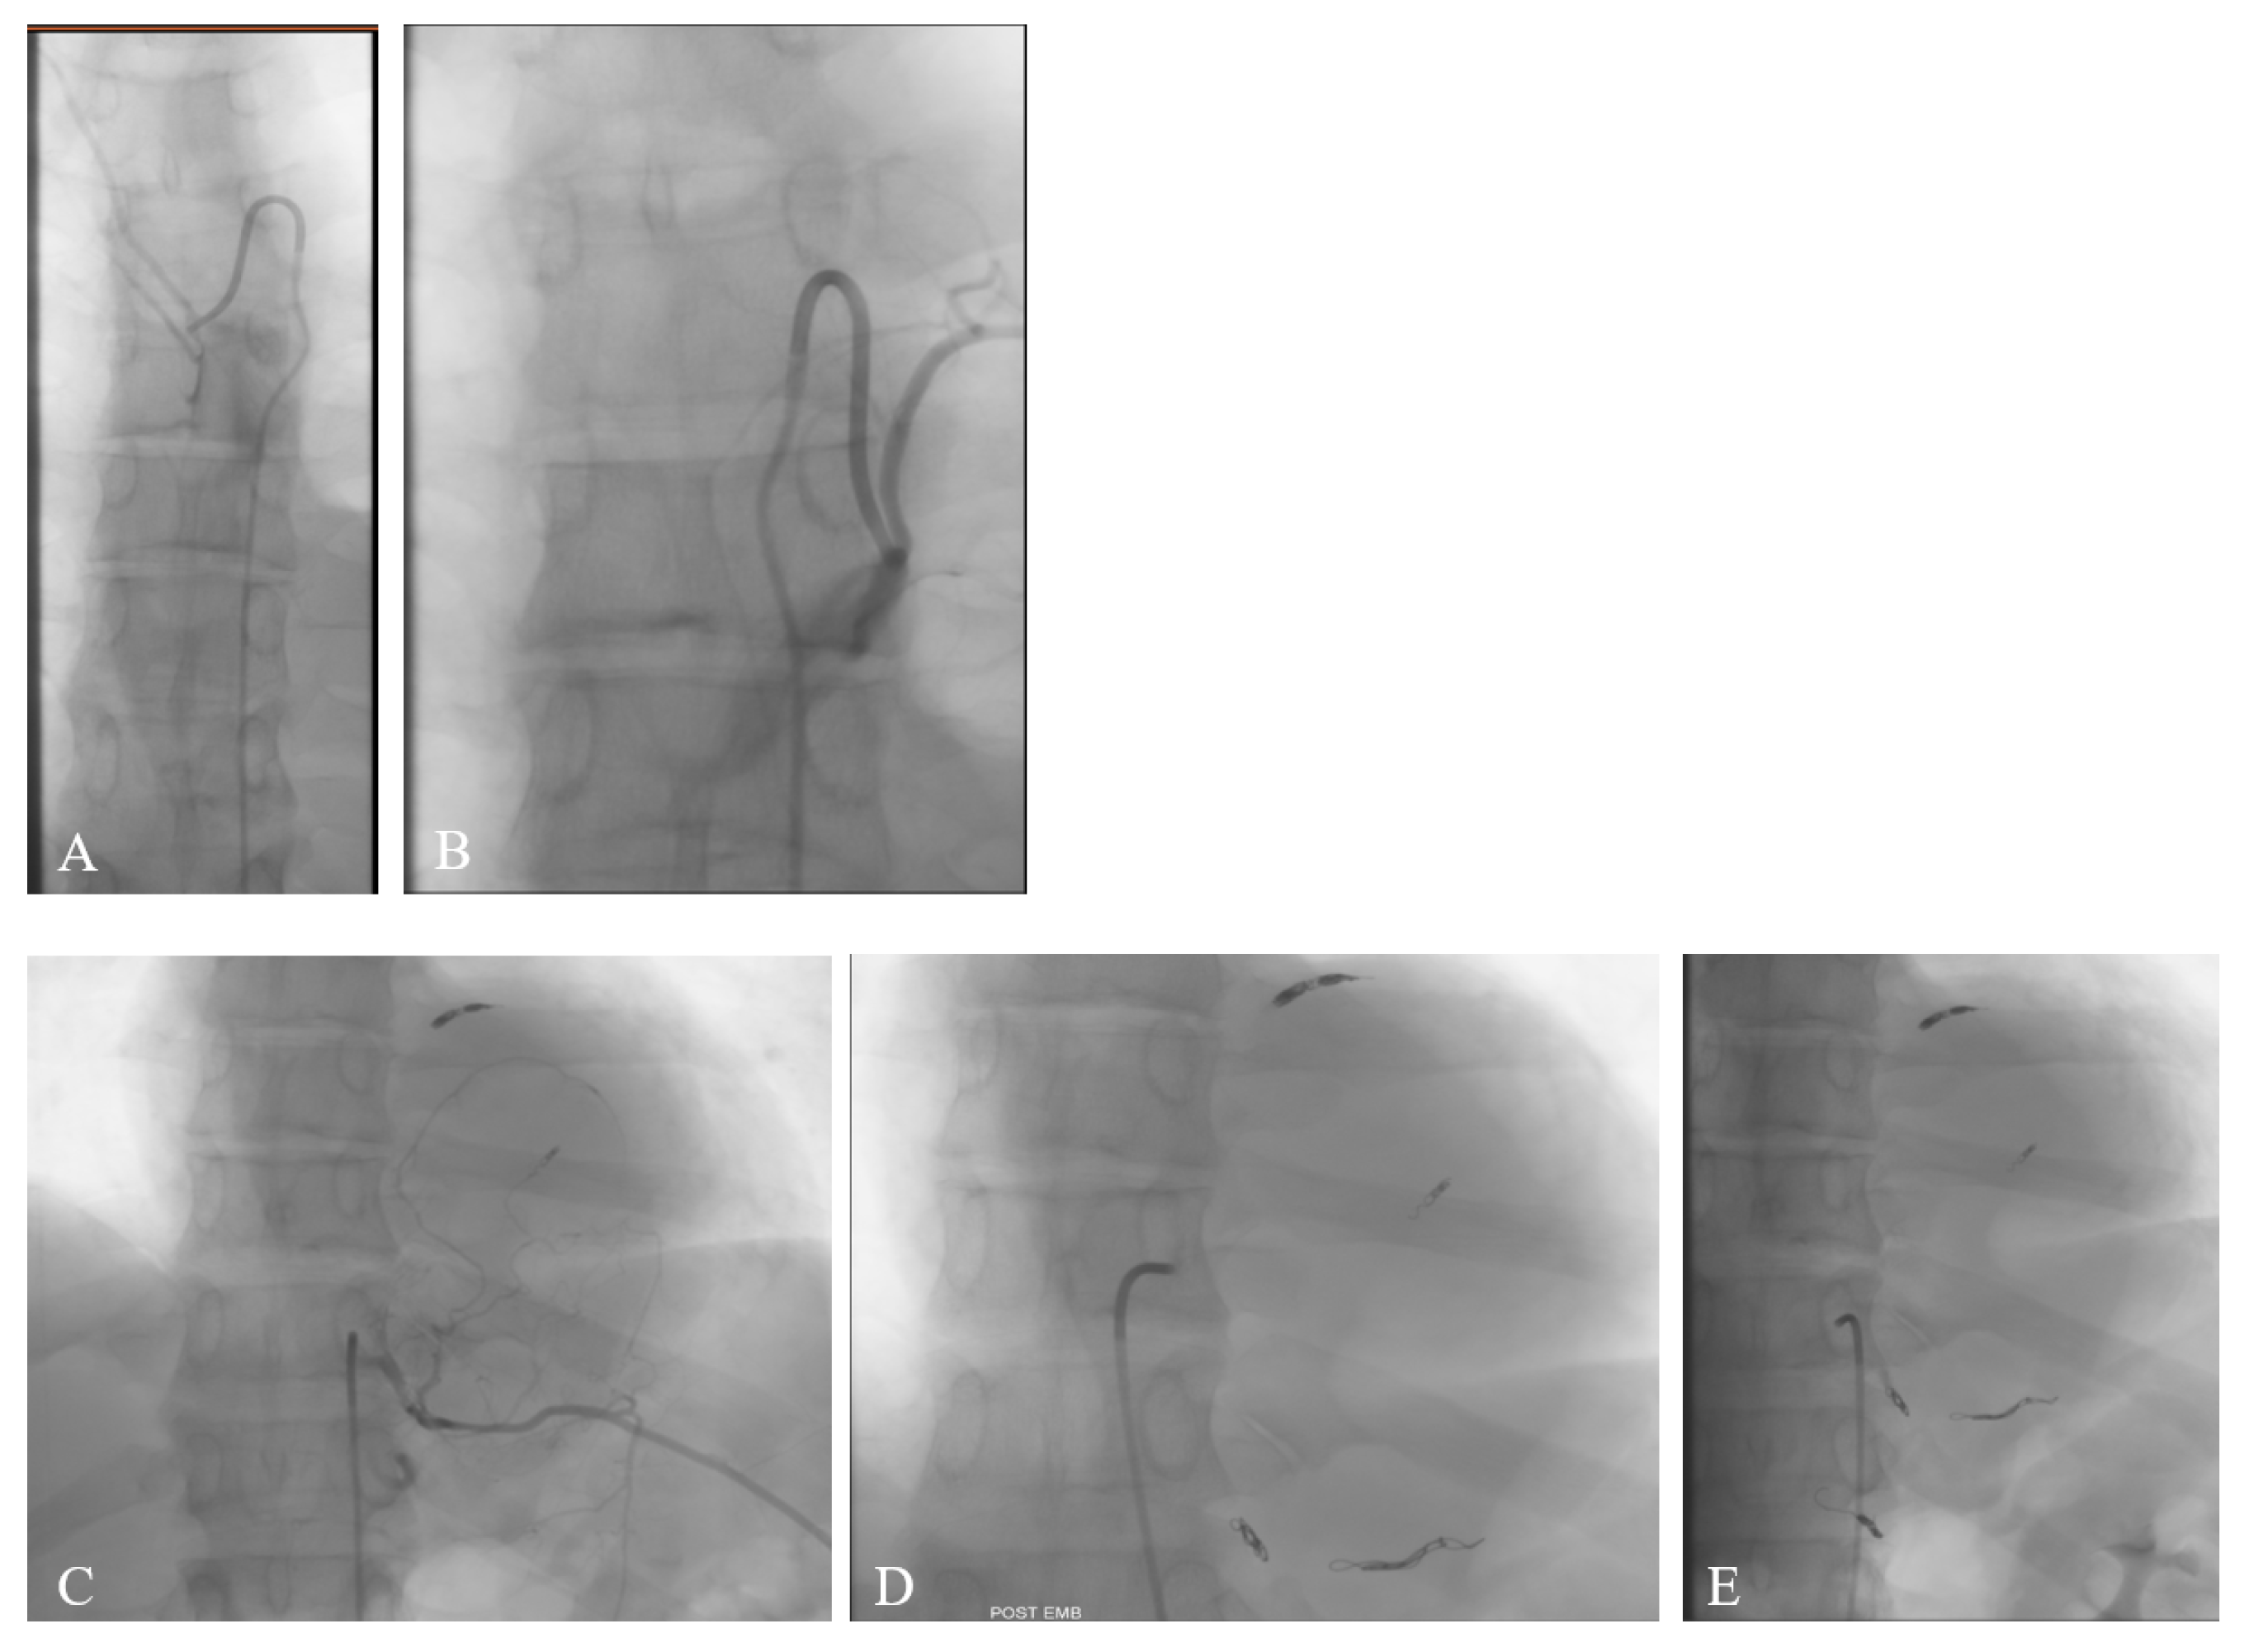

2. Case Report